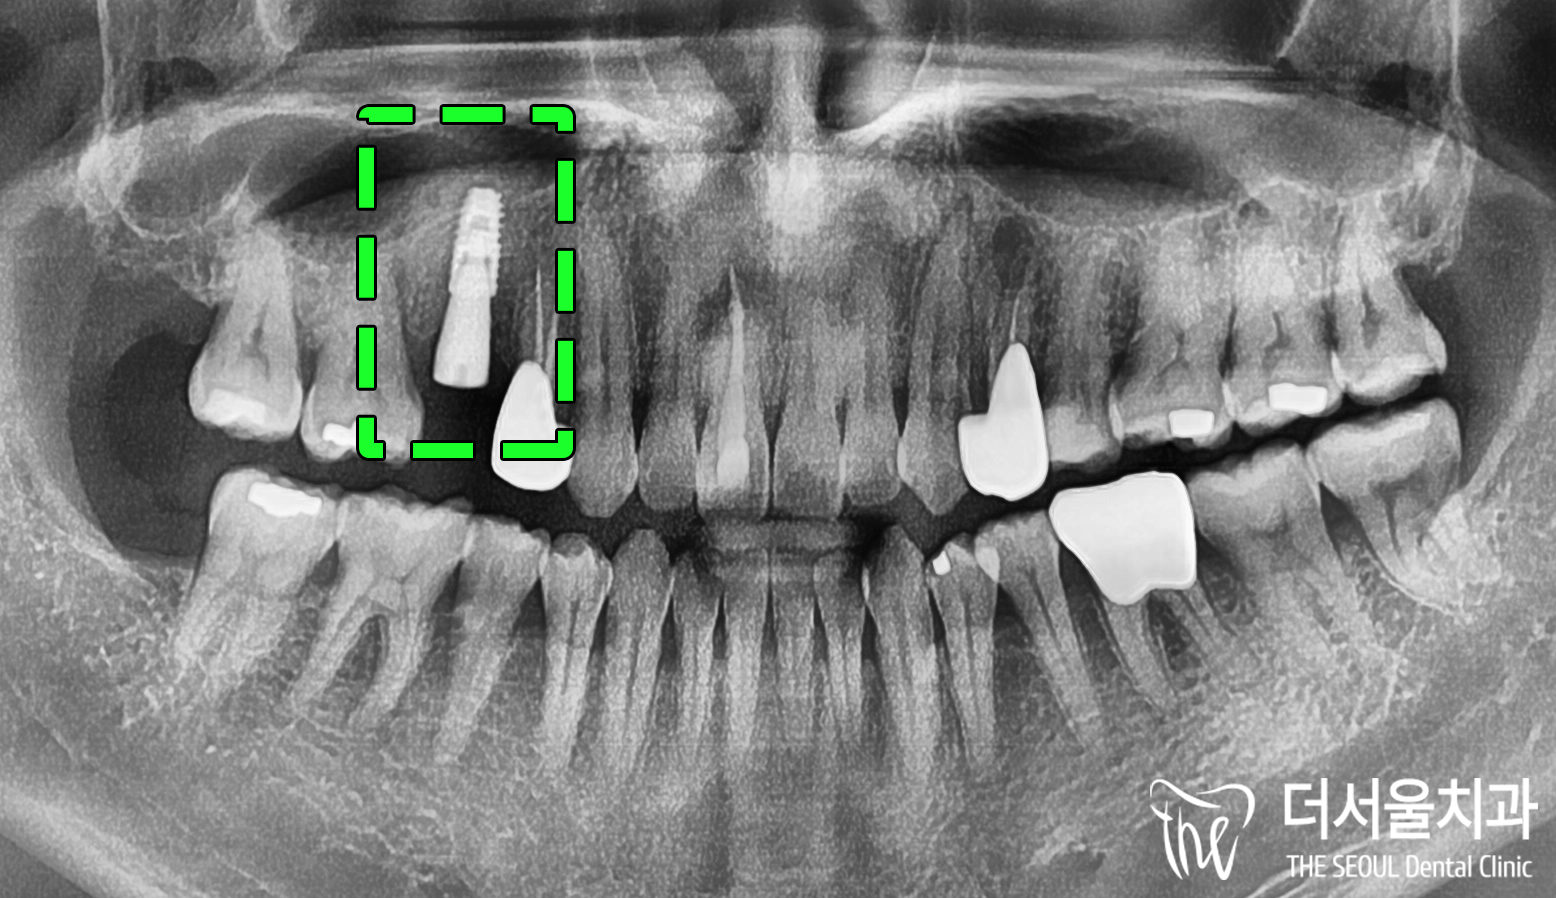

문제 되는 부분을 함께 보겠습니다.

15번 소구치는 이미 발치되어있습니다.

겉으로 봤을 때는

그렇게 뼈가 많이 없어진 것 같지는 않습니다.

겉으로 봐서는 자세히 알 수 없기에

더 정확한 진단이 필요하여

CT 촬영 및 분석에 들어갑니다.